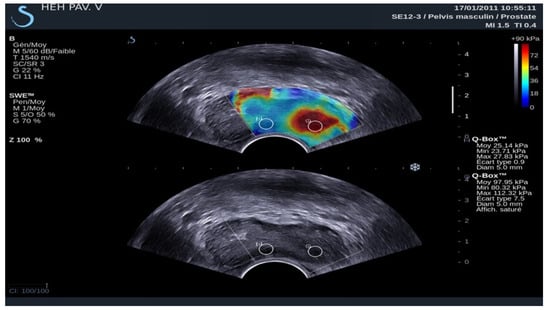

3.3. Elastography in Prostate Lesions